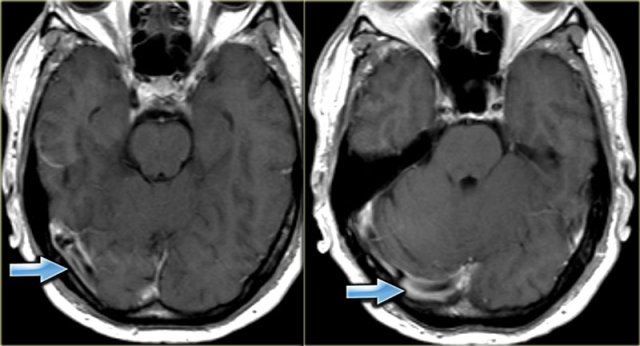

On the left there is a thrombosed right transverse sinus with a delta sign on the contrast enhanced image.

The sinus has a low signal intensity on the T2-weighted image as a result of the intracellular deoxyhemoglobin.

On the contrast enhanced T1-weighted image it is obvious that the sinus is filled with thrombus.

On the contrast enhanced T1 images on the left there is an area of low signal intensity within the enhancing transverse sinus.

This could easily been mistaken for a central thrombus within the sinus.

This however is the result of flow void.

Continue with the phase contrast images.

On the phase contrast images it is obvious that the transverse sinus is patent.